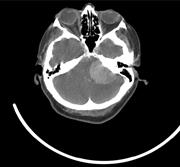

Unilateral vocal cord palsy and dysphagia: an unusual presentation of cerebellopontine angle meningioma

Andrew Senior and others

Journal of Surgical Case Reports, Volume 2015, Issue 10, October 2015, rjv129, https://doi.org/10.1093/jscr/rjv129